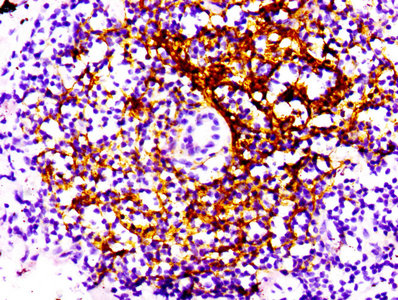

CD34 Antibody (CSB-RA004926A0HU)

IHC image of the antibody diluted at 1:100 and staining in paraffin-embedded human kidney tissue performed on a Leica BondTM system.

CD4 Antibody (CSB-RA004935A0HU)

IHC image of the antibody diluted at 1:100 and staining in paraffin-embedded human spleen tissue performed on a Leica BondTM system.

CD44 Antibody (CSB-RA004938A0HU)

IHC image of the antibody diluted at 1:100 and staining in paraffin-embedded human tonsil tissue performed on a Leica BondTM system.

CD21 Antibody (CSB-RA005934A0HU)

IHC image of the antibody diluted at 1:100 and staining in paraffin-embedded human lung cancer performed on a Leica BondTM system.